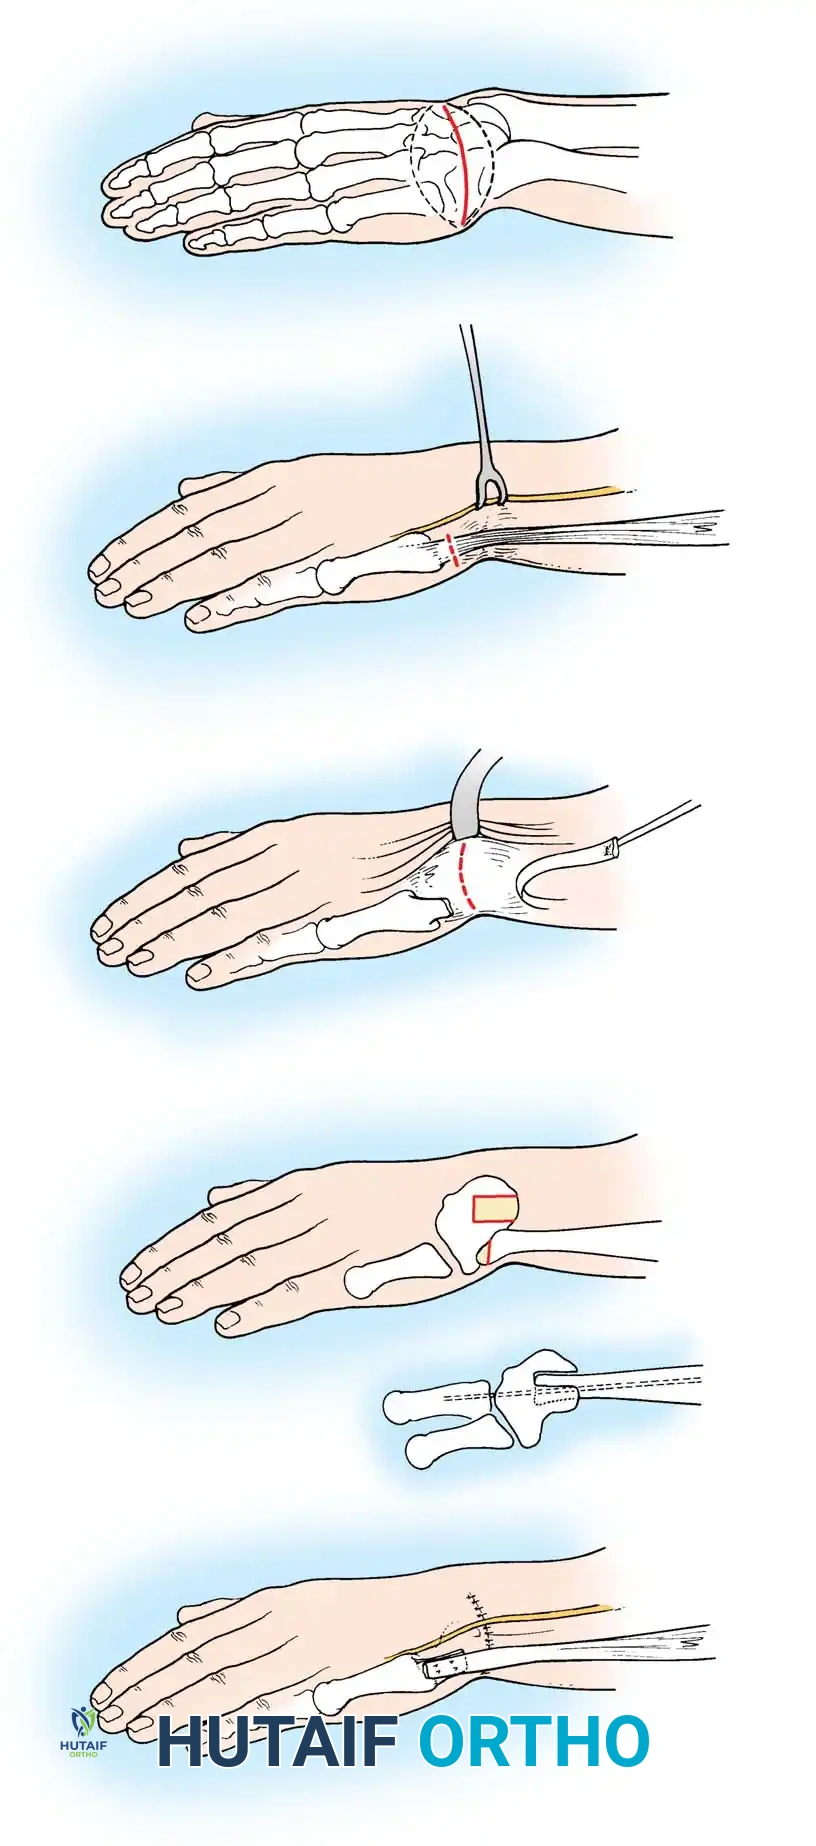

Fig. 76-3 A and B. Early fitting of a passive prosthesis in a child with a congenital forearm amputation is critical to encourage incorporation of the prosthesis into the child's body image.

1. 3 to 6 Months (Sit to Fit): A passive plastic mitten prosthesis is introduced once the child achieves independent sitting balance. This provides stability during sitting and assists in pulling to a stand.

2. 12 to 18 Months: The passive mitten is exchanged for an actively opened, plastisol-covered split hook. A Child Amputee Prosthetic Program (CAPP) terminal device may be substituted. Training with the functional device begins immediately.

3. 2 to 4 Years: A myoelectrical prosthesis may be considered. Studies have shown these to be highly useful and appropriate for preschool-aged children, offering superior cosmesis and intuitive grip control.

4. 3 Years and Older: For above-elbow amputations, dual-terminal devices and articulated elbow controls (friction elbows) are introduced.

Surgical Warning: Prosthetic management for midcarpal amputations remains controversial. The long, below-elbow stump is exceptionally useful for stabilizing objects and bimanual function because it retains native sensibility. Sacrificing terminal sensibility for a cosmetic artificial hand must be carefully weighed against the functional loss.